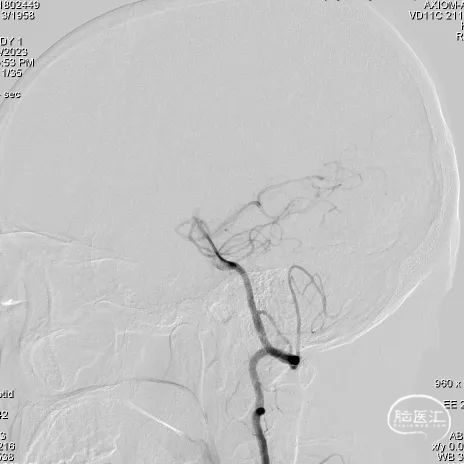

左侧椎动脉造影

右侧椎动脉3D旋转

右侧椎动脉造影

① 右侧椎动脉V4段夹层动脉瘤伴血栓形成;

① 支架头端、尾端锚定位置的选择;

② 瘤颈处血管稍狭窄,可能影响支架展开和贴壁效果;

③ 夹层动脉瘤,瘤腔内伴血栓形成,超选过程中存在血栓脱落的风险。

长鞘到位后工作角度造影;尽量暴露双椎汇合部,方便术中判断支架头端锚定位置。

V4段夹层动脉瘤伴瘤腔内血栓形成,瘤体较大,密网支架可有效降低手术难度和术后复发率。

支架头端锚定位置尽量不要覆盖基底动脉近端,术中支架头端打开顺利,锚定血管壁牢靠,未出现支架头端下移和前移的情况。

血栓性质夹层动脉瘤,不仅需要通过造影评估动脉瘤显影情况、支架贴壁情况;术前和随访需查头颅磁共振,评估瘤体(瘤壁)大小的变化。